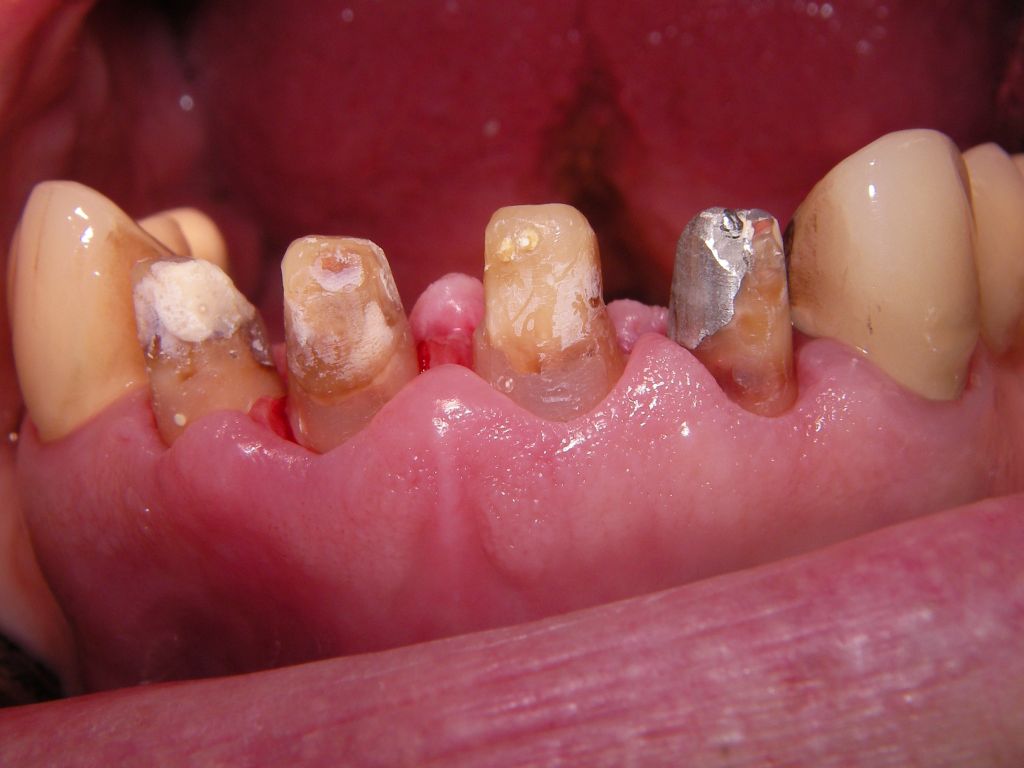

Eine Vollkeramikkrone (Keramik ohne Metallunterbau) ist demgegenüber bruchanfälliger. Der Vorteil der Vollkeramikkrone ist allerdings, daß bei Rückgang des Zahnfleisches auch nach vielen Jahren kein dunkler Metallrand sichtbar werden kann. Allerdings kann man diesen Metallrand auch sehr schmal gestalten, wie das folgende Beispiel zeigt. Wegen der starken Zerstörungen mußte der Kronenrand tief unter das Zahnfleisch gelegt werden. Das ist einerseits ungünstig, weil es Zahnfleischentzündungen fördern kann (die hier aber nicht zu sehen sind), andererseits günstig, weil nicht zu befürchten ist, daß das Zahnfleisch so weit zurückgehen wird, daß man den Kronenrand sehen wird. Wenn man nicht so weit unter das Zahnfleisch mit dem Kronenrand gehen muß und mehr Platz hat, kann man auch einen keramischen Rand (eine "keramische Stufe") wählen. Das erhöht die Laborkosten, aber man hat die Sicherheit, daß es langfristig keinen sichtbaren Metallrand geben kann. Auch eine Vollkeramikkrone ist natürlich möglich. Oft ist nach vielen Jahren aber gar nicht die Krone das Problem, sondern die dunkle Zahnwurzel, die vom Zahnfleisch entblößt wird. Wie man unten sieht, sind insbesondere wurzelbehandelte Zähne sehr dunkel. Hier hilft dann doch nur wieder, mit dem Kronenrand tief unter das Zahnfleisch zu gehen, um die dunkle Wurzel abzudecken. Patient, 67 Jahre. Die Bilder sind alle zur Vergrößerung anklickbar! |

Weil auch die anderen Schneidezahnkronen (12-22) durch Randreparaturen und den schlechten Randschluß erneuerungsbedürftig aussahen, wurden 4 Einzelkronen geplant. Vorher hieß es aber noch, die schlechte Wurzelfüllung im Zahn 12 (Röntgenbild links) besser zu machen. Hierfür wurden am 17.2.06 die alten Kronen 11 und 12 entfernt. Rechts das Bild nach Entfernung von alten Füllungen und Karies. | |